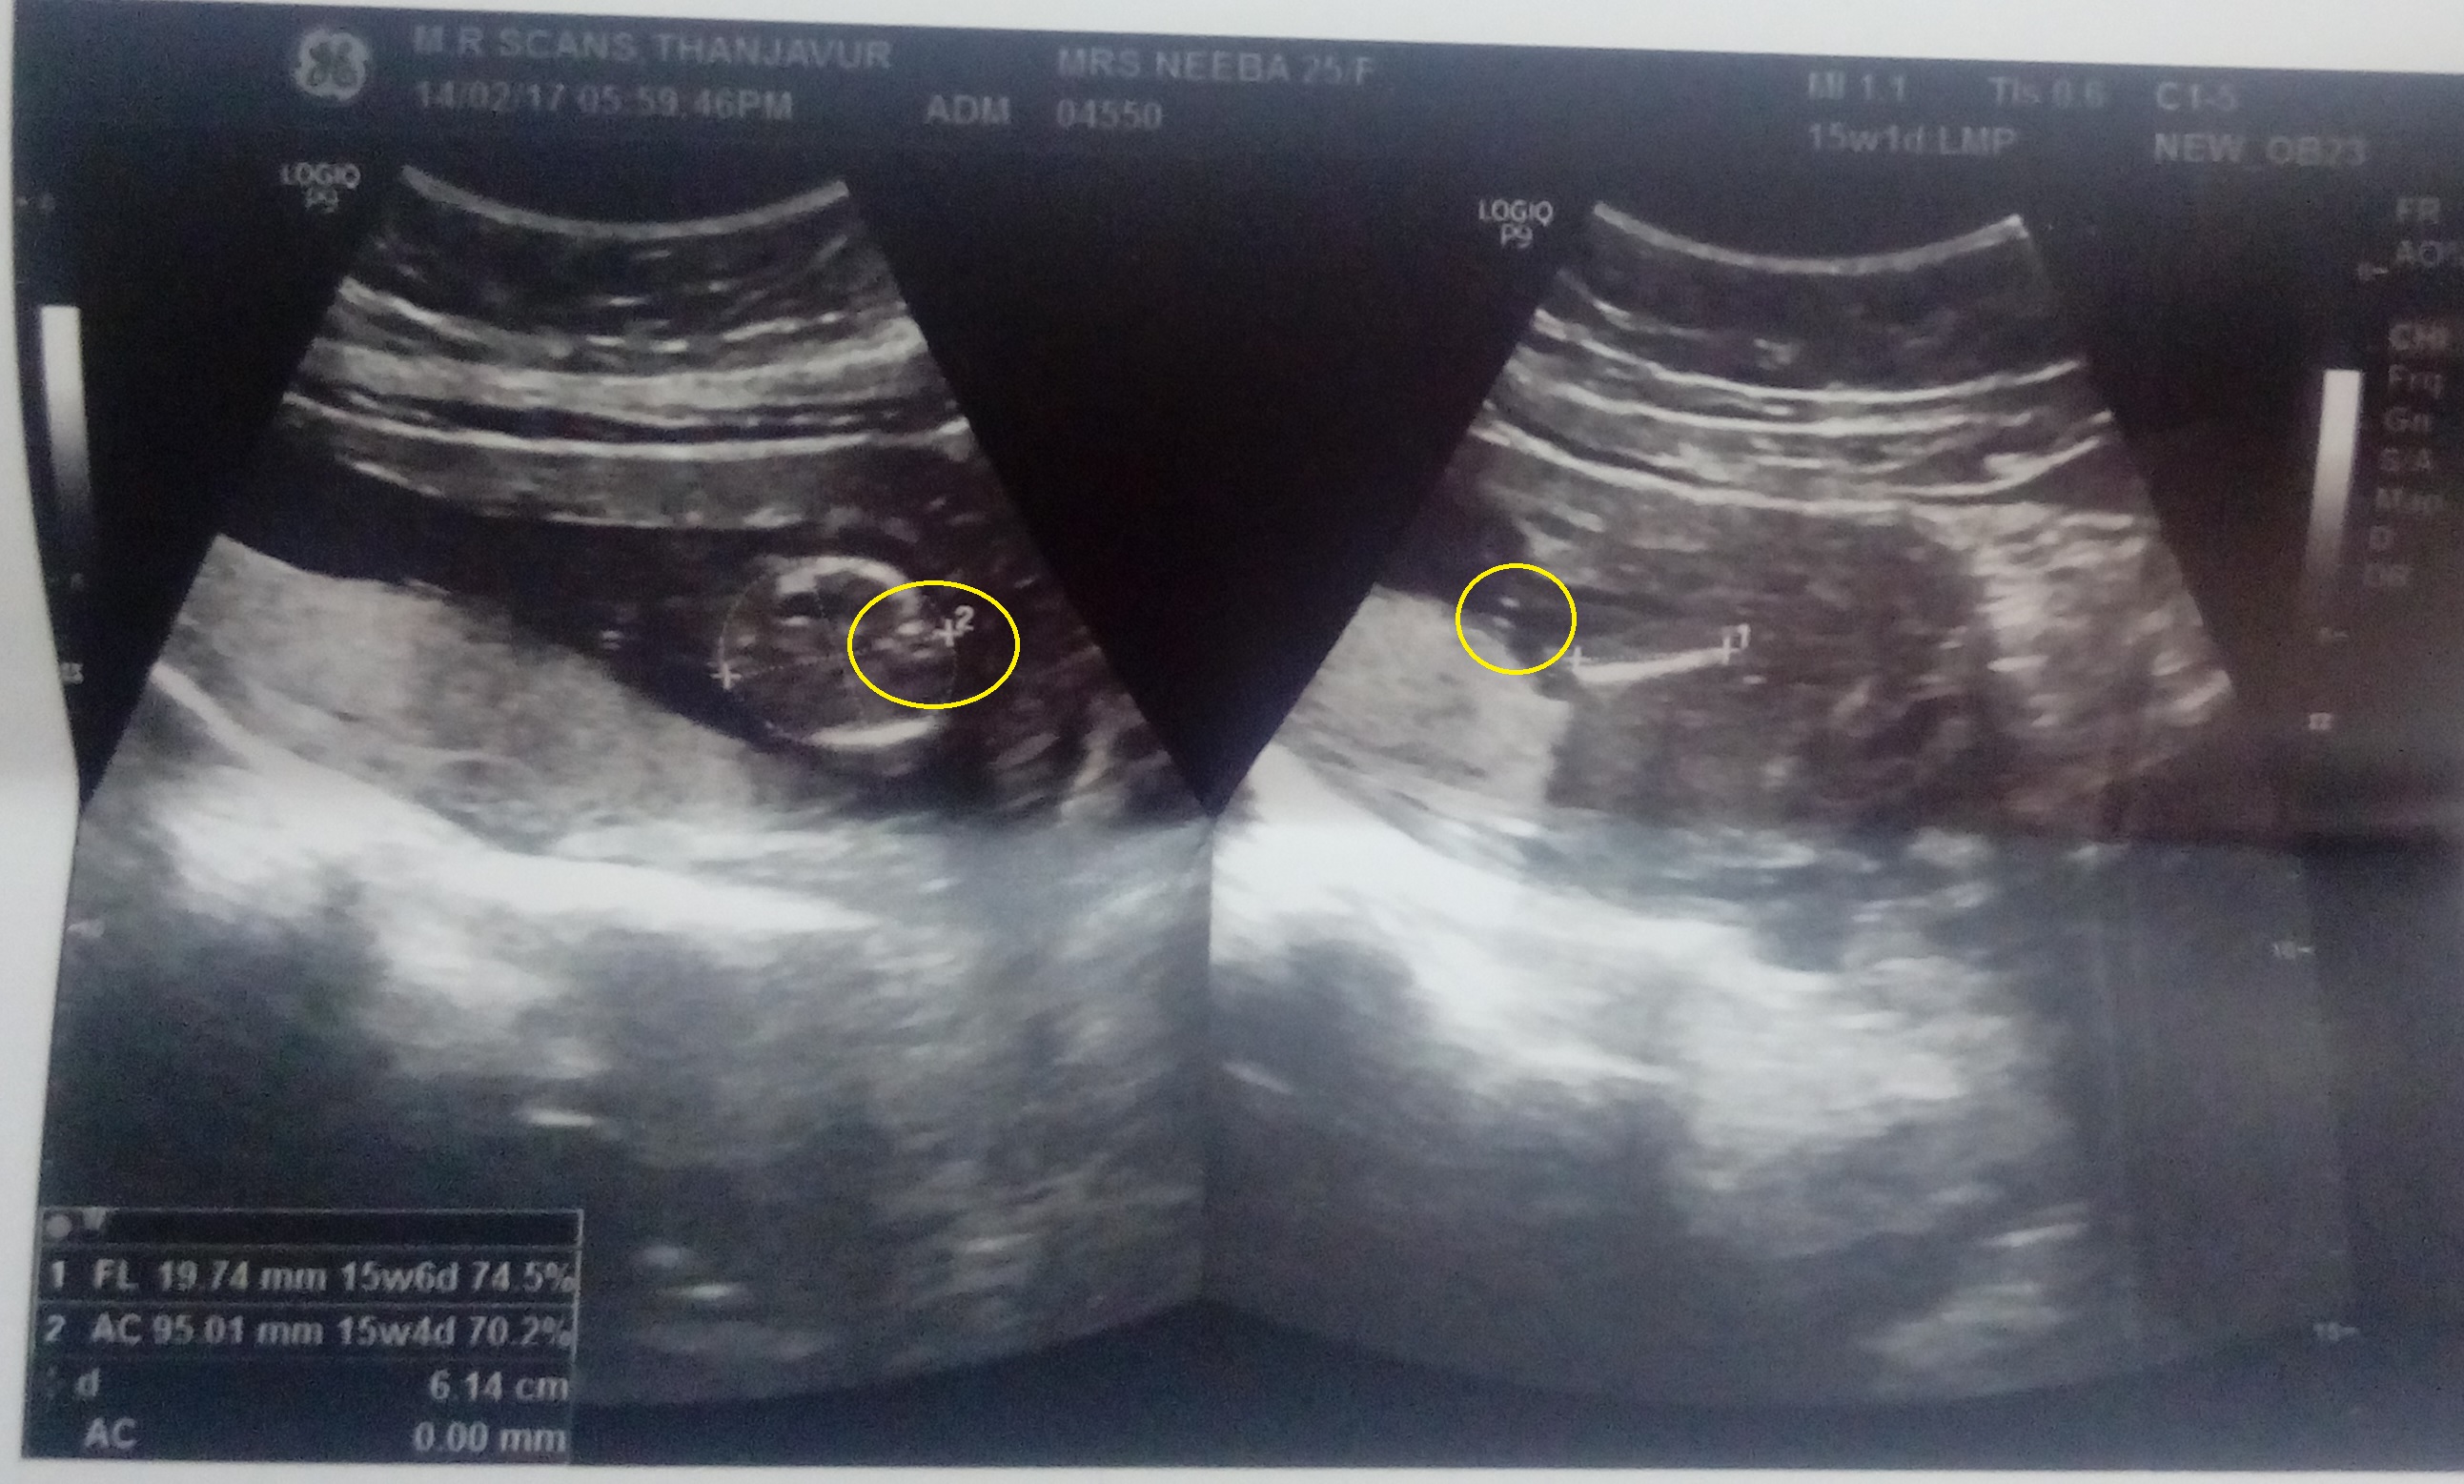

im very much confusedAttachment 35438, i could see both nubs

and another one, all of the images were taken at 15 weeksAttachment 35439

I think the only one that MAYBE shows gender is the second to last pic (the one on the left). Maybe girl, but there is writing there covering the gender, so I'm not sure.